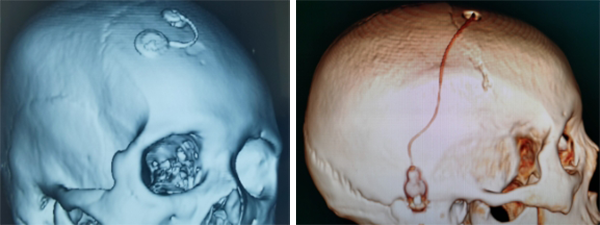

脑膜转移主要表现为头痛头晕、恶心呕吐、复视、视物模糊、走路不稳、共济失调、癫痫、肢体麻木疼痛等症状。10位患者术前的脑脊液细胞学均找到癌细胞,5例通过Ommaya囊脑室植入术、2例腰大池腹腔分流术、3例Ommaya囊脑室植入术联合腰大池腹腔分流术。术后联合鞘内化疗、靶向治疗后,患者临床症状明显改善。

脑膜转移检出率大约为5%-8%,肺癌是最常见的原发肿瘤,其次为乳腺癌、黑色素瘤。未经治疗的中位生存期仅4-6周。临床表现常见为高颅压、癫痫、视物模糊、颅神经及脊神经受累症状。脑膜转移的诊断以脑脊液细胞学找到癌细胞为金标准。Ommaya囊脑室植入术不但可以引流脑脊液降低颅内压,还可以为脑室内实施化疗创建通道,避免了反复腰穿打药的痛苦。腰大池腹腔分流术及侧脑室腹腔分流术可以通过皮下管路将脑脊液引流入腹腔经腹膜吸收,与穿刺Ommaya囊进行脑脊液外引流相比,该方法增加了患者的舒适度,更有利于改善患者生活质量。